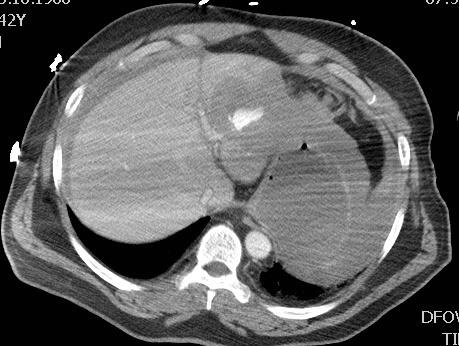

外伤后肝左叶实质出血 |